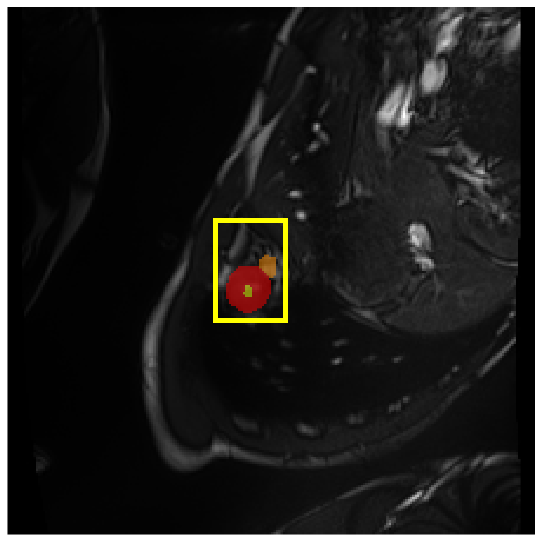

Medical image segmentation plays a critical role in various diagnostic workflows, as it enables accurate delineation of anatomical structures and pathological regions, thereby enhancing disease interpretation, treatment planning, and outcome prediction. Jang et al. [1] has demonstrated that improved segmentation performance can lead directly to reduced diagnostic error rates and increased clinician confidence. Building on the remarkable success of deep learning across diverse domains [2, 3, 4, 5], recent progress in medical image segmentation has been primarily driven by deep learning. Since the introduction of U-Net [6], segmentation methods have rapidly evolved, with convolutional neural networks (CNN)-based models [7, 8, 9] and Transformer-based models [10, 11, 12] showing superior performance in computed tomography (CT) and magnetic resonance imaging (MRI) segmentation. However, various challenges such as blurriness, noise, and low contrast often hinder the accurate diagnosis of diseases. Applying various image enhancement techniques to generate an enhanced image from the input can alleviate this problem, as existing methods have demonstrated improved segmentation accuracy [13, 14, 15]. Nevertheless, input images may unintentionally lose crucial information contained in the original image during enhancement. As a result, the segmentation model suffers from performance degradation (Fig. 1(a) and (b)). Therefore, we argue that it is crucial to leverage the advantages of both the original and enhanced images through image fusion strategies.

4.3.2 Visual Comparisons

Visualization of our method on the Synapse and ACDC datasets is shown in Fig. 3(a) and Fig. 3(b). For the Synapse dataset illustrated in Fig. 3(a), FCT failed to accurately segment SM and GB, while MERIT achieved precise segmentation of SM but struggled with GB. In contrast, our method achieved accurate segmentation of both SM and GB. Regarding the ACDC dataset shown in Fig. 3(b), while previous methods achieve comparable segmentation of the Myo and LV to the GT, they exhibit noticeable errors on the RV, including invasion into adjacent organs and misrecognition. On the other hand, our method accurately segments across all three structures Myo, LV, and RV, performing as precisely as the GT. We demonstrate the superiority of our method quantitatively and qualitatively.